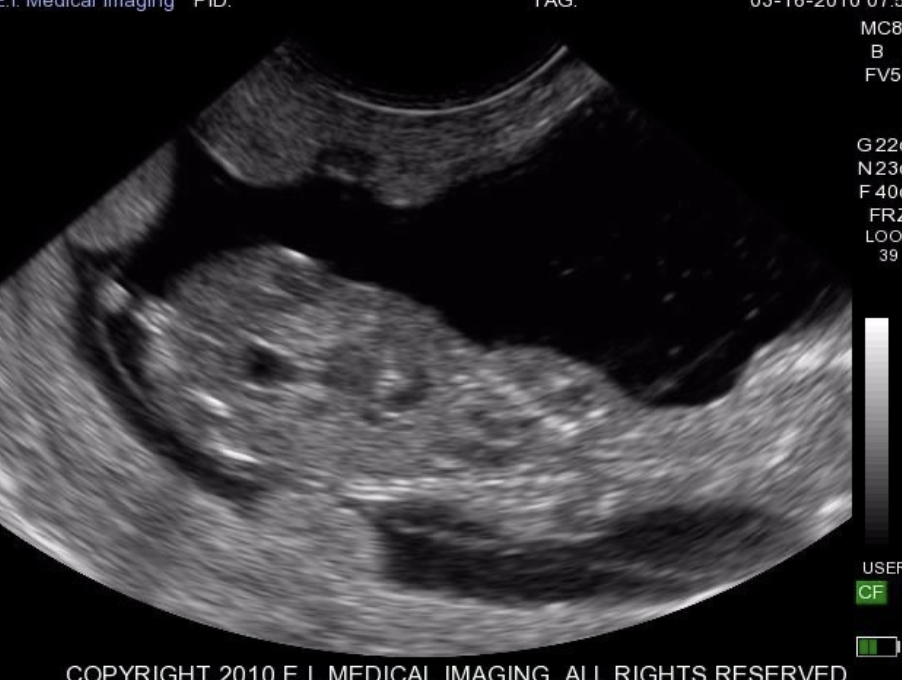

how is pregnancy diagnosed via ultrasound?

using b-mode, real time, and a linear probe

-use 7.5MHz for early diagnosis >26 days

-use 5MHz for later diagnosis >35 days

embryo is observed by day 26-29

when can fetal sexing be performed via ultrasound?

at about 60 days gestation (image is of 61d - female)

what are the ultrasonographic signs used for determining fetal sex of calves?

by observing where the genital tubercle is:

-near umbilicus= male

-under tail= female